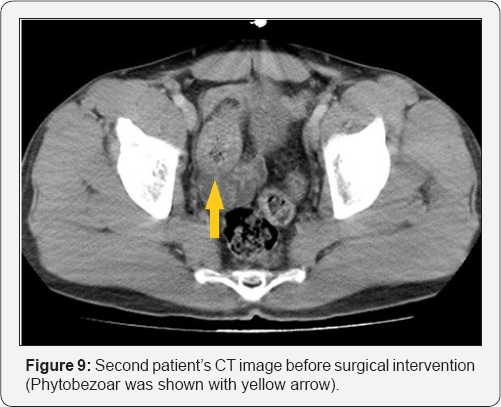

A 35-year-old male patient presented with the complaints of severe abdominal pain, nausea and vomiting for approximately six hours was evaluated in the emergency department. We learned from the history that the patient, who did not have any concomitant disease or previous surgery, had eaten lots of fruits with solid consistency without chewing too much. The patient, who had diffuse abdominal distention on physical examination, had increased bowel sounds and diffuse abdominal tenderness. Laboratory results showed no other pathological finding other than leukocytosis (12500/mm3). The urgent abdominal CT of the patient performed for the purpose of determining the ileus etiology revealed a phytobezoar-related obstruction in the ileum and dilatation in the proximal loops (Figure 9).

Clinically, patients present with obstruction findings, such as abdominal distention, abdominal pain, nausea and vomiting [1]. Direct x-rays, the firstline diagnostic techniques, may provide visualization of ileus findings, such as air-fluid levelings, as well as free air in cases of perforation. However, they are not sufficient to reveal the etiologic cause [1]. The abdominal CT is an important diagnostic tool with a sensitivity rate of 90% and a specificity rate of 96%. Well-demarcated intra-luminal mass with air bubbles, along with dilated intestinal loops and collapsed loops following mass can be visualized in CT [7]. In our first case, a gastric phytobezoar that migrated after the endoscopy was visualized in the jejunal loops in the tomographic images (Figures 1-4). Whereas in our second case, bezoar causing obstruction in the ileum was visualized (Figure 5).